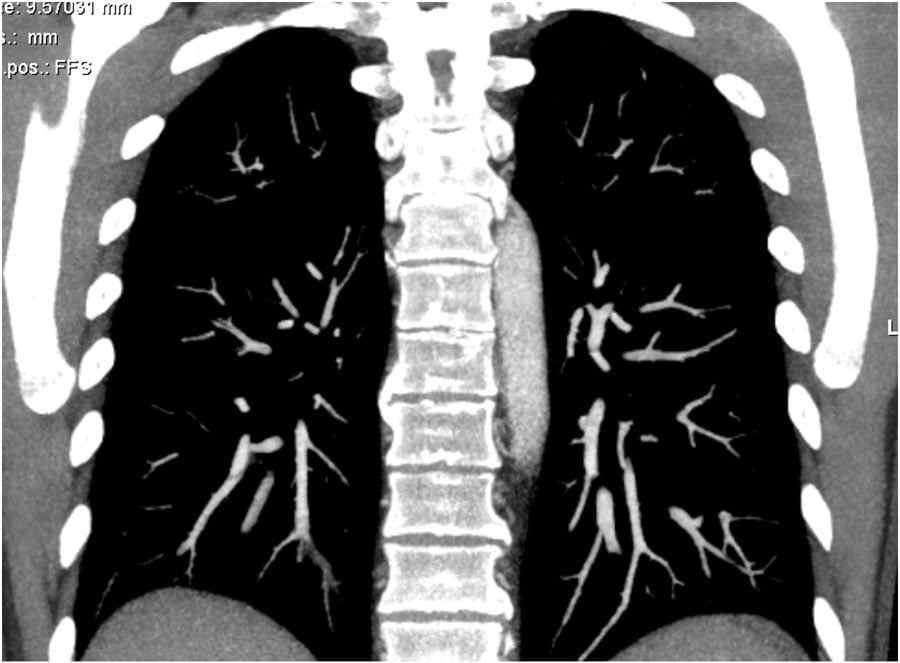

Good quality CT scanning is the most important factor for the diagnosis of pulmonary emboli. On a poor quality scan it is impossible to rule out emboli.

We prefer to scan from bottom to top, because if a patient can’t hold his breath, then you will have less breathing artefacts in the lower lobes, where most of the emboli are located. In the upper lobes breathing does not cause that much movement as in the lower parts of the lung.

We ask the patient to breath in normally and hold his breath to avoid the transient interruption of contrast, which will be explained in a moment.

Cần máy CT chất lượng tốt. Máy CT chất lượng kém không cho phép loại trừ thuyên tắc.

Chúng tôi thường quét từ vùng đáy lên đỉnh phổi, vì bệnh nhân nếu không nín thở tốt thì artefact cũng ít xảy ra ở vùng đáy phổi. Đa số các thuyên tắc là ở vùng đáy phổi. Hô hấp ở phần trên ít gây artefact so với vùng dưới của phổi.

Lúc đầu nói bệnh nhân thở đều bình thường (không nên thở mạnh và sâu) và khi chụp nói bệnh nín thở.

For good timing bolus tracking is needed.

A ROI is placed in the pulmonary trunk.

When the treshhold of 150 HU is reached, the patient is asked to breath in and scanning is started immediately.

Để chọn đúng thời điểm chụp, cần có bộ phận theo dõi nồng độ thuốc (bolus tracking).

Đặt con trỏ (ROI) vào vị trí thân động mạch phổi.

Khi nồng độ thuốc đạt tới 150 HU, nói bệnh nhân hít vào và nín thở, chụp ngay sau đó.

Thick MIP reconstructions can be helpful in following the vessels and detecting emboli.

Hình tái tạo MIP dày cho phép theo dõi và phát hiện thuyên tắc.